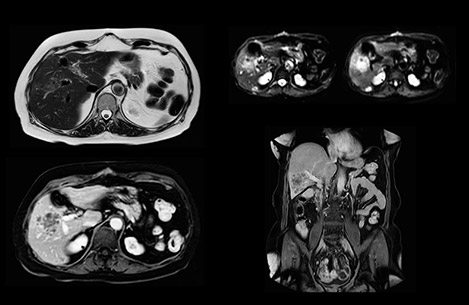

“Our liver exams are quite fast,” says Dr. Baumann. “If the patient tolerates it, we use an arms-up position to reduce the FOV and speed up the exam with dS SENSE.” “We acquire one transversal high resolution T2-weighted sequence with 3 mm slice thickness, for example for pancreas or liver lesions. Then we also add a T2 fat suppressed MultiVane XD SPIR sequence. We perform these two routinely in our liver imaging. We use high dS SENSE factors to significantly shorten scan times to 2-4 minutes, which can improve our protocol; it’s a very robust scan.” “We include mDIXON for the dynamic sequences because of the robust and homogeneous fat suppression we get with that. We had been using eTHRIVE, but we are now quite happy with mDIXON. Sometimes we use a medication to calm the bowels, to further improve the image quality.”

“We are more confident in our diagnosis if we don’t have to rescan the patient and compare it to other studies; this liver exam gives us good image quality in a faster time than the default system’s approach with arms down. That makes a difference for the patients, too. The shorter scan times, especially with the high dS SENSE factors, shorten the duration of the total examination. At the same time it’s more comfortable for the patient, to rest normally without holding the breath, just relaxing.”